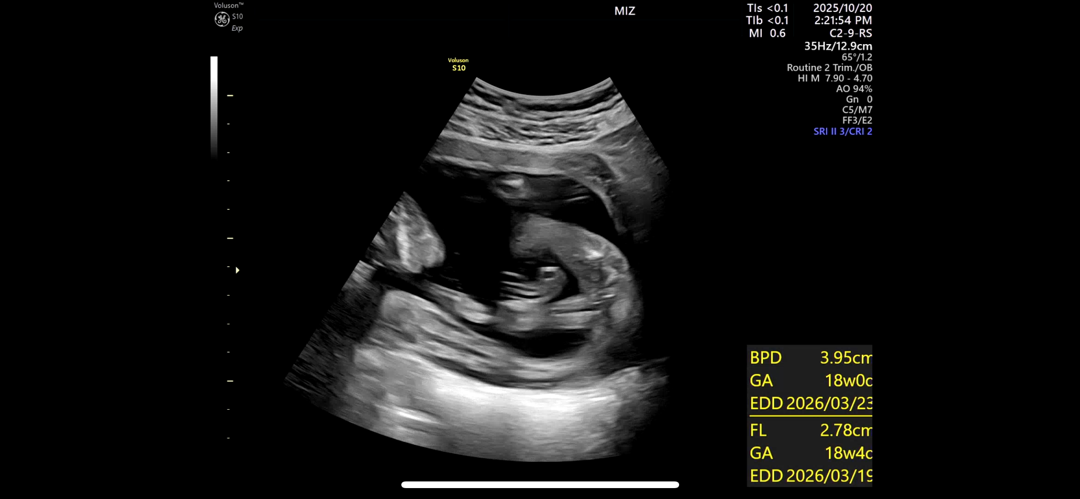

예비 아들맘으로서.. 아들이라면 숨길 수 없는 꼬츄가 확연하게 보여요🌶

지인중 비슷하게 임신 하신 분 3분 다 성별 벌써 들었는데 저는 갈때마다 엉덩이 콕 숨기고 다리를 예쁘게 꼬고 있어서 2번 다녀왔는데 계속 어려워 하시더라구요 초음파 영상 캡쳐한 건데 그냥 제 똥촉으로는 딸인 거 같거든요..! 의사 선생님은 정확하지 않대요 흐려서 뽕알이 안보이는 거일수도 있다고 하네요 마미들이 봤을때는 어떤가요..?

흐려도 존재감이 뿜뿜한다는 거죠 ㅋㅋㅋ 미치겠네요 별 쇼 다 해봤는데 다리는 꼼짝도 안 하다니 ㅜㅜ